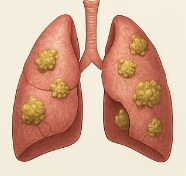

폐암 초기증상이란 폐에서 발생하는 암세포가 아직 크지 않고 주변 조직이나 장기로 전이되지 않았을 때 나타나는 증상을 말합니다. 폐암 초기증상은 뚜렷하지 않아 단순 감기나 피로로 오해하기 쉽습니다. 그러나 폐암 초기증상을 조기에 발견하면 치료 성과가 크게 달라집니다.

폐암은 진행 속도가 빠르고 전이 가능성이 높습니다. 따라서 폐암 초기증상을 아는 것은 생존율 향상에 결정적입니다. 폐암 초기증상을 무시하면 병이 진행되어 발견될 때는 이미 수술이 불가능한 경우가 많습니다. 즉, 폐암 초기증상에 대한 관심과 조기 발견은 생명을 지키는 핵심 요소입니다.